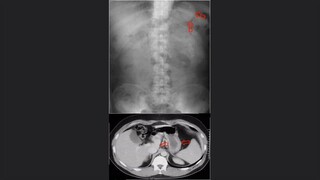

Generalidades del tórax y pulmón